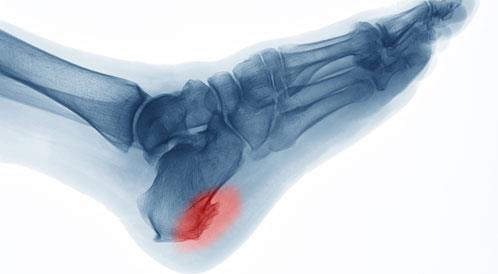

يعد مسمار الكعب أو الشوكة العظمية أحد أكثر أسباب آلام القدم شيوعا ويظهر نتيجة ترسبات كلسية تتكون عند نقطة ارتباط الرباط الأخمصي بعظمة الكعب وعلى الرغم من  أنه قد لا يكون خطيرًا في معظم الحالات، إلا أنه يؤثر بشكل واضح على الحركة اليومية وجودة الحياة، خاصة عند المشي أو الوقوف لفترات طويلة. يوضح الدكتور أشرف نبيل استشاري أمراض العظام أن المشكلة تبدأ بسبب إجهاد متكرر للقدم، سواء نتيجة ممارسة الرياضة العنيفة أو الوقوف لساعات طويلة أو ارتداء أحذية غير مناسبة، كما تلعب زيادة الوزن والتهابات اللفافة الأخمصية دورًا كبيرًا في تحفيز تكون هذا النتوء العظمي ويعد الأشخاص الذين يعانون من مشاكل في مرونة عضلات الساق أو لديهم تاريخ من إصابات القدم أكثر عرضة للإصابة. وأضاف  أن أبرز أعراض مسمار الكعب تتمثل في ألم حاد يشبه الطعن عند الخطوات الأولى صباحا وقد يخف تدريجيا مع الحركة لكنه يعود مع الإجهاد المتكرر، كما قد يصاحب الألم شعور بالوخز أو شد في عضلات الساق أو انتشاره نحو القدم أو الكاحل. يعتمد العلاج في أغلب الحالات على الراحة وتمارين الإطالة ووضع كمادات باردة واستخدام أحذية طبية ذات دعم مناسب وقد يحتاج البعض إلى جلسات علاج طبيعي أو حقن مضادة للالتهاب في الحالات الأكثر شدة ويعد التدخل الجراحي الخيار الأخير عندما تفشل العلاجات الأخرى.